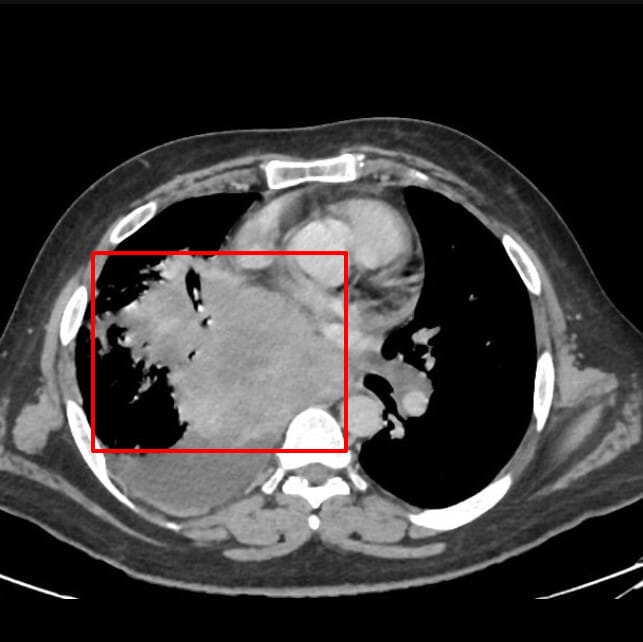

흉부 CT 소견

주로 폐 중심부에 발견, 종격동 림프절 비대 동반

소세포폐암 진단 및 병기 결정에 가장 중요한 영상 검사입니다.

| 중심부 종괴(central mass) |

| 폐문(hilum) 또는 기관지 근처에 조영 증강되는 덩어리성 병변 |

| 종격동 림프절 비대 |

| 대칭적으로 비대해진 림프절이 흔하며, 빠르게 전이됨 |

| 기관지 협착 또는 폐쇄 |

| 종양이 기관지를 압박하거나 막아 폐허탈(무기폐) 유발 |

Glick Y, Small cell lung cancer. Case study, Radiopaedia.org (Accessed on 20 Apr 2025) https://doi.org/10.53347/rID-161374

영상 소견상 특징

- Right lung hilum 쪽에 Large mass with necrotic foci

- Complete RML collapse.

- Large RLL consolidation and interstitial thickening in rest of lobe.

- Large right pleural effusion.